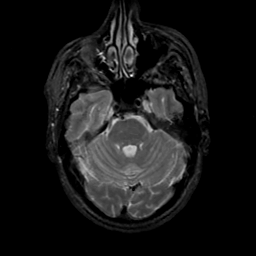

MR Study #17, July 7, 1991 -- Slice #14

[Home][Help][Clinical][Tour 1][Tour 2] Slice 14